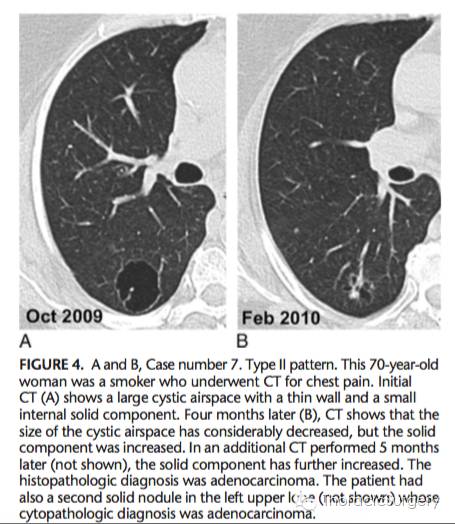

II型患者CT随访: 医学百科网 | YxBaike.Com

II型患者的3年CT随访: